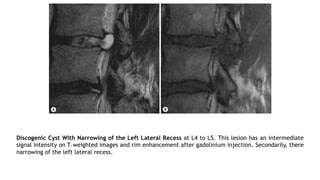

Discogenic Cyst With Narrowing of the Left Lateral Recess at L4 to L5. This lesion has an intermediate

signal intensity on T1 weighted images and rim enhancement after gadolinium injection. Secondarily, there

narrowing of the left lateral recess.